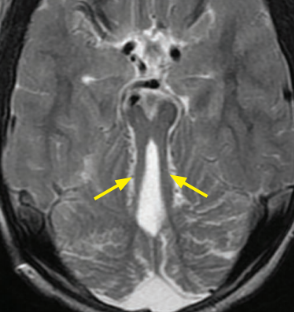

- Hypoplasie du vermis cérébelleux

- Aspect en “Molar Tooth”